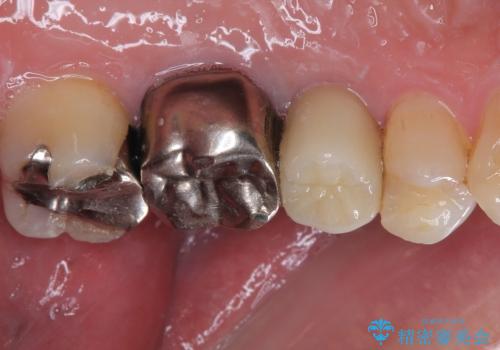

抜歯が必要な小臼歯 インプラントによる補綴治療

- 頻繁に銀歯が外れてしまうとのことで来院された患者様です。

歯肉の中、深いところまでむし歯が進行しており、歯根を部分矯正で引っ張り出してから補綴治療を行うか、抜歯してインプラント補綴治療を行うか選択することになりました。

ジルコニアカスタムアバットメントは、歯肉ラインに金属が見えにくいというだけでなく、クラウンを装着する土台の形が天然歯と近い形態となるため、清掃性が高く歯肉が腫れにくいというメリットがあります。

インプラントは、骨との生着能が比較的高いとさせるSLAタイプを使用しました。